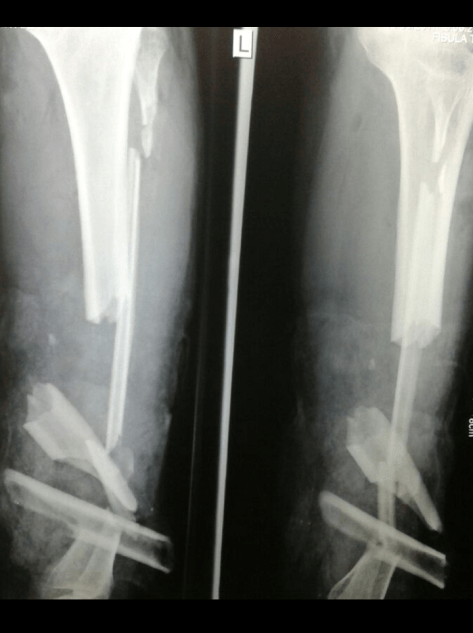

Patah Tulang Paha (Femur Fracture)

Patah tulang paha atau fraktur femur berbeda dengan patah tulang lainnya. Jika dibiarkan tanpa pengobatan yang tepat fraktur femur sangat mungkin tidak akan menyambung (nonunion) atau jika sangat beruntung menyambung tetapi dalam posisi yang tidak anatomis (malunion). Karakteristik paha dengan adanya otot (muscle belly) yang besar, demikian pula adanya kekuatan tarikan otot (muscle contractions) yang kuat menyebabkan pemendekan dan ketidakstabilan (unstable) posisi patahan tulang sehingga sulit untuk mencapai proses penyambungan tulang (bone healing). Jika ditangani secara tepat sesuai standar prosedur penanganan maka kemungkinan tulang akan menyambung (union) sebesar 90% dengan kemungkinan membaik tanpa adanya infeksi sebesar 99%.1

image

Satu waktu seorang remaja pria datang kepada saya, kira-kira 16-an tahun usianya. Dia murid kelas 2 SMU di sebuah kota, bertubuh tinggi berperawakan atletis cocok dengan hobinya bermain basket. Ibu bapaknya guru SMU dan salah satunya adalah guru Biologi. Dia datang dengan jalan pincang dan lutut kanan yang tidak bisa ditekuk sempurna. Setengah tahun sebelumnya dia mengalami kecelakaan motor. Oleh ayahnya dia dibawa ke pengobat alternatif patah tulang (bone setter) terkemuka di kota tersebut.

Hingga berbulan sesudahnya keadaan tidak semakin membaik. Setelah dilakukan pemeriksaan X-ray (ronsen) ternyata dia mengalami patah tulang paha yang tidak menyambung (nonunion fracture of supracondyler femur). Menghadapi kasus patah tulang terabaikan (neglected fracture) seperti demikian tim dokter bedah tulang tidak bisa memberi harapan maksimal kepada mereka. Kemungkinan besar range of movement tidak akan kembali normal kalaupun ketidakseimbangan panjang kaki (LLD/leg legth discrepancy) dapat diminimalisir. Keinginannya yang kuat untuk dapat bermain basket dan menjadi atlet sepertinya akan sulit terwujud. Akan sangat berbeda jika patah tulang yang dulu dialaminya segera ditangani. Kecacatan yang mungkin saja bisa dicegah dengan prinsip terapi orthopedi yang bisa dipertanggungjawabkan secara ilmiah dan moral.

Sangat disayangkan orangtua yang terpelajar itu masih percaya dengan pengobatan non medis yang tidak dapat dipertanggungjawabkan secara ilmiah. Semoga semakin banyak masyarakat yang sadar akan pentingnya membawa problem tulang dan anggota gerak badan (muskuloskeletal) kepada tim dokter bedah tulang. Terlebih dengan adanya jaminan kesehatan oleh pemerintah diharapkan akan semakin banyak pasien yang bisa tertangani, terlepas dengan segala kekurangan yang tentunya diharapkan terus kita perbaiki bersama-sama.